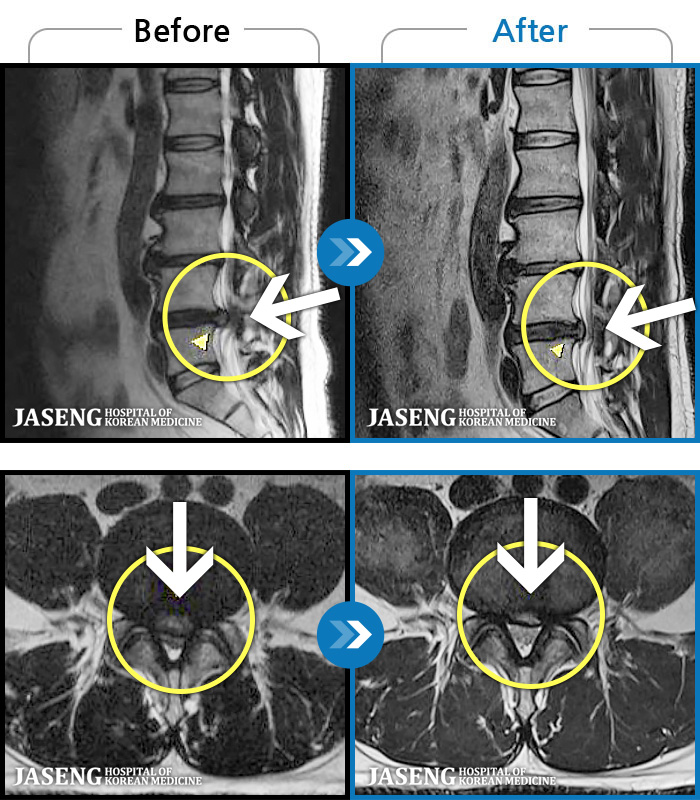

1,240 MRI ũ ʸ Ȯϼ.

| [뱸] 19.11.28~25.05.06